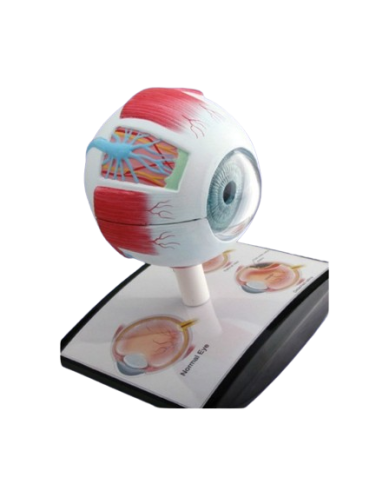

Modello anatomico PER FORNITURE CASE FARMACEUTICHE

Modello anatomico PER FORNITURE CASE FARMACEUTICHE

Modello anatomico PER FORNITURE CASE FARMACEUTICHE

Modello anatomico PER FORNITURE CASE FARMACEUTICHE

Modello anatomico PER FORNITURE CASE FARMACEUTICHE

Modello anatomico PER FORNITURE CASE FARMACEUTICHE

Modello anatomico PER FORNITURE CASE FARMACEUTICHE

Modello anatomico PER FORNITURE CASE FARMACEUTICHE

Modello anatomico PER FORNITURE CASE FARMACEUTICHE

Modello anatomico PER FORNITURE CASE FARMACEUTICHE

Modello anatomico PER FORNITURE CASE FARMACEUTICHE

Modello anatomico PER FORNITURE CASE FARMACEUTICHE

Modello anatomico PER FORNITURE CASE FARMACEUTICHE

Modello anatomico PER FORNITURE CASE FARMACEUTICHE

Modello anatomico PER FORNITURE CASE FARMACEUTICHE

Modello anatomico PER FORNITURE CASE FARMACEUTICHE

Modello anatomico PER FORNITURE CASE FARMACEUTICHE

Modello anatomico PER FORNITURE CASE FARMACEUTICHE

Modello anatomico PER FORNITURE CASE FARMACEUTICHE

Modello anatomico PER FORNITURE CASE FARMACEUTICHE

Modello anatomico PER FORNITURE CASE FARMACEUTICHE

Modello anatomico PER FORNITURE CASE FARMACEUTICHE